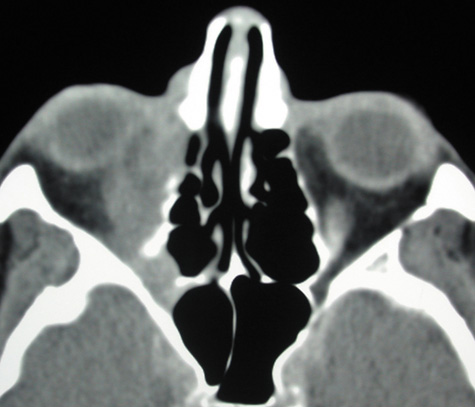

CT is particularly useful for imaging orbital and subperiosteal abscesses. Because the periorbit is not adherent to the orbital walls except at the suture lines, an abscess lifts the periorbit, creating a convexity in the orbital periosteum (Fig. 16). Usually subperiosteal abscess formation occurs adjacent to the involved sinus,25,64 but occasionally it occurs at a remote location such as the superolateral orbit.65 Gas may be found within a subperiosteal abscess or within the orbit, arising either from gas-forming bacilli or free communication with sinus air or from prior trauma (Fig. 17). 57,66 CT cannot accurately predict whether a subperiosteal mass represents exudate, inflammatory transudate, or hematoma.67,68

Fig. 16. Computed tomography showing subperiosteal abscess formation. Note elevation of orbital periosteum and convexity as pus elevates periorbit from the medial orbital wall.